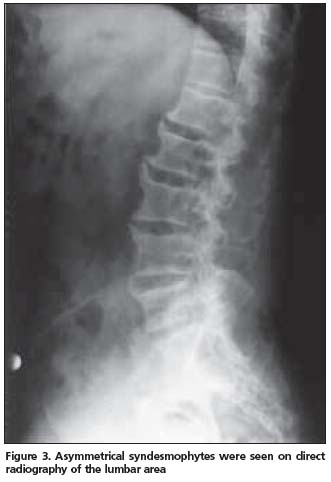

Anterior longitudinal ligament calcification, fusion of multiple facet joints and atypical syndesmophytes were found on cervical spine X-rays (Figure 1) and coarse, asymmetrical syndesmophytes were seen on thoracic (Figure 2) and lumbar spine (Figure 3) X-rays. No abnormalities suggesting PsA or gout were seen on hand and foot radiographs. The magnetic resonance imaging (MRI) of the sacroiliac joint and computerized tomography (CT) of atlanto-axial joint were normal.

PsSpA is observed in 5% of the PsA patients and may be clinically confused with AS[12]. The clinical characteristics of our case also resembled AS. An inflammatory type of low back pain was present and chest expansion was 2 cm. X-rays revealed a predominance of axial involvement. However, a normal sacroiliac joint MRI and lack of a typical syndesmophyte appearance made the AS diagnosis unlikely.

Another striking radiologic finding in our patient was that cervical spine involvement was on the foreground. Queiro et al. reported the cervical spine involvement in HLA-B27- negative PsSpA patients to be 51%[13]. Cervical spine involvement in PsA is known to be seen more commonly in patients presenting with psoriatic lesions on hairy skin[12]. The majority of skin lesions were localized on the hairy skin in our patient. Radiographic abnormalities are not sufficiently sensitive and specific for the diagnosis of gout. Only 45% of patients with gout manifest radiographic bone changes, and then only six to eight years after the initial attack. The radiographic hallmarks of gout are normal mineralization, joint space preservation, sharply marginated erosions with sclerotic borders, overhanging edges, and asymmetric polyarticular distribution[14]. Radiologic evaluation of our patient did not reveal any of these images.